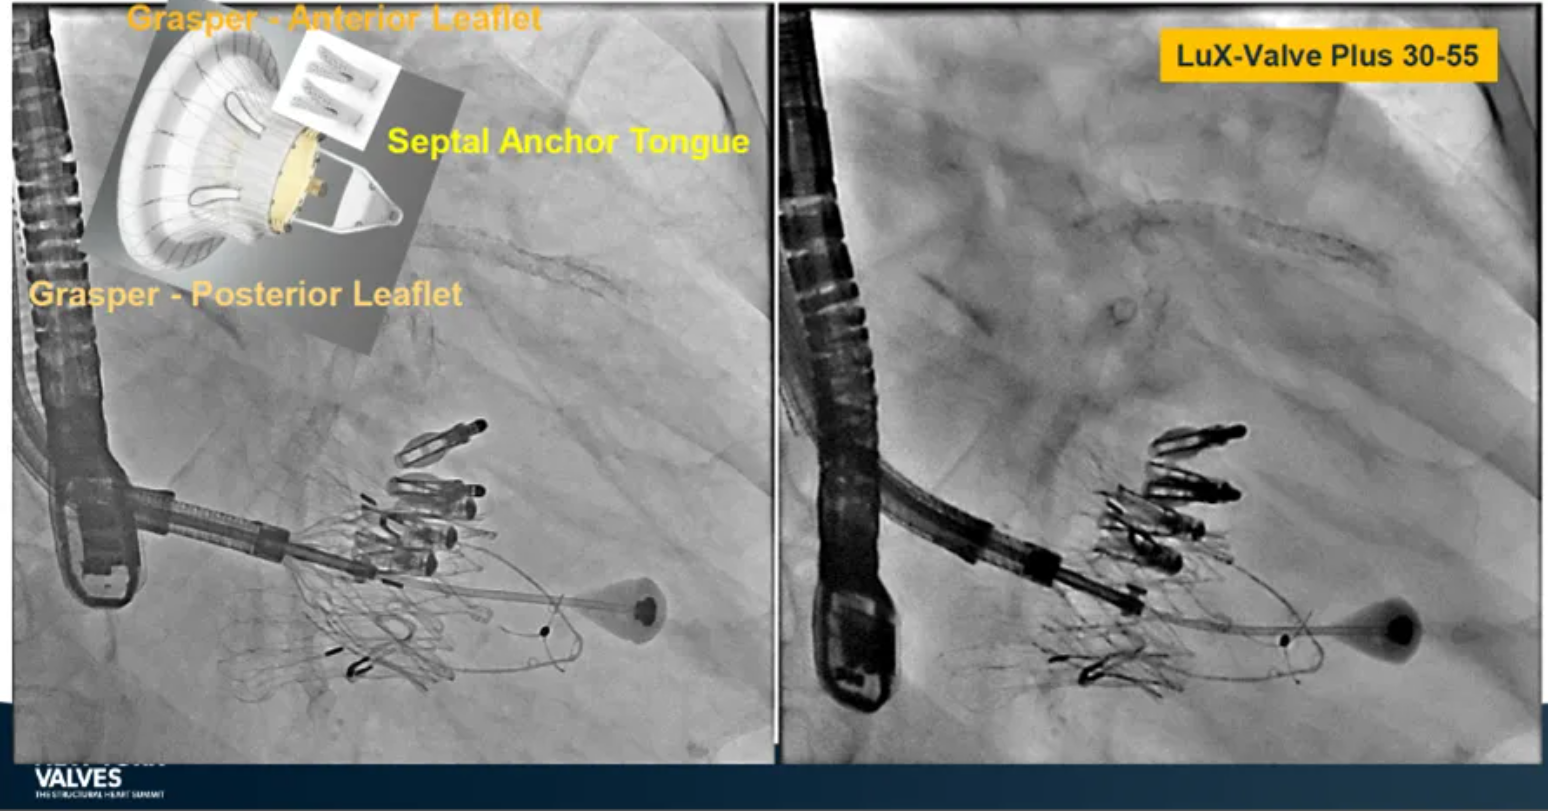

LuX-Valve Plus是健世科技(Jenscare,9877.HK)推出的全新一代經(jīng)頸靜脈三尖瓣置換系統(tǒng)(Transjugular Tricuspid Valve Replacement System),其創(chuàng)新性地采用頸靜脈作為手術(shù)入路,在不依賴徑向支撐力的情況下借助室間隔錨定、瓣葉夾持技術(shù)構(gòu)成其多重錨定結(jié)構(gòu),并通過自適應(yīng)編織環(huán)有效進(jìn)行心房側(cè)封堵,呈現(xiàn)更好的安全性和有效性。

來自中國(guó)香港瑪麗醫(yī)院(Queen Mary Hospital, Hong Kong, China)的Simon Lam教授在2024年紐約瓣膜會(huì)上分享了一例復(fù)雜案例,一名高齡男性患者在2年前行二尖瓣和三尖瓣TEER術(shù)式后繼發(fā)三尖瓣反流,遂再次行二尖瓣TEER術(shù)式和用LuX-Valve Plus行三尖瓣TTVR術(shù)式。

本次術(shù)式中,LuX-Valve Plus的植入緊隨二尖瓣修復(fù)術(shù)式之后,且并未取出前期植入的三尖瓣修復(fù)夾,這意味著LuX-Valve Plus在患者有過二尖瓣和三尖瓣修復(fù)夾植入情況下的兼容性,并且?guī)砹擞行У闹委熃Y(jié)果。此外,這不僅體現(xiàn)了LuX-Valve Plus可以與二尖瓣術(shù)式并行,更可以兼容三尖瓣原位的其他修復(fù)夾產(chǎn)品。